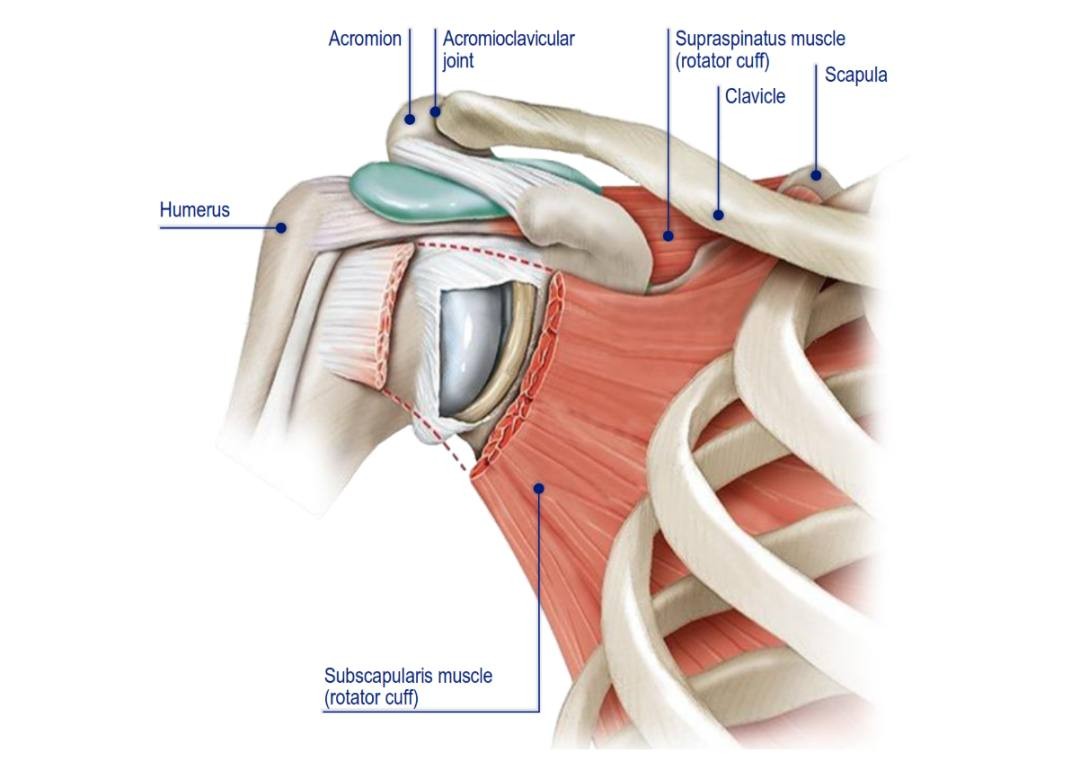

先进肩关节置换植入系统提供商:Shoulder Innovations, Inc.(SI

项目类型

器械质押区

起投金额

20000USDT

每日释放:2

释放周期:150 天

已购: 4900

剩余: 0